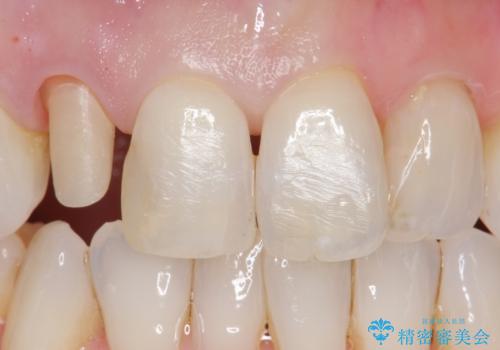

前歯が取れてしまった ジルコニアクラウンでの修復

他の歯との調和のとれたクラウンを装着することができ大変喜んでいただけました。